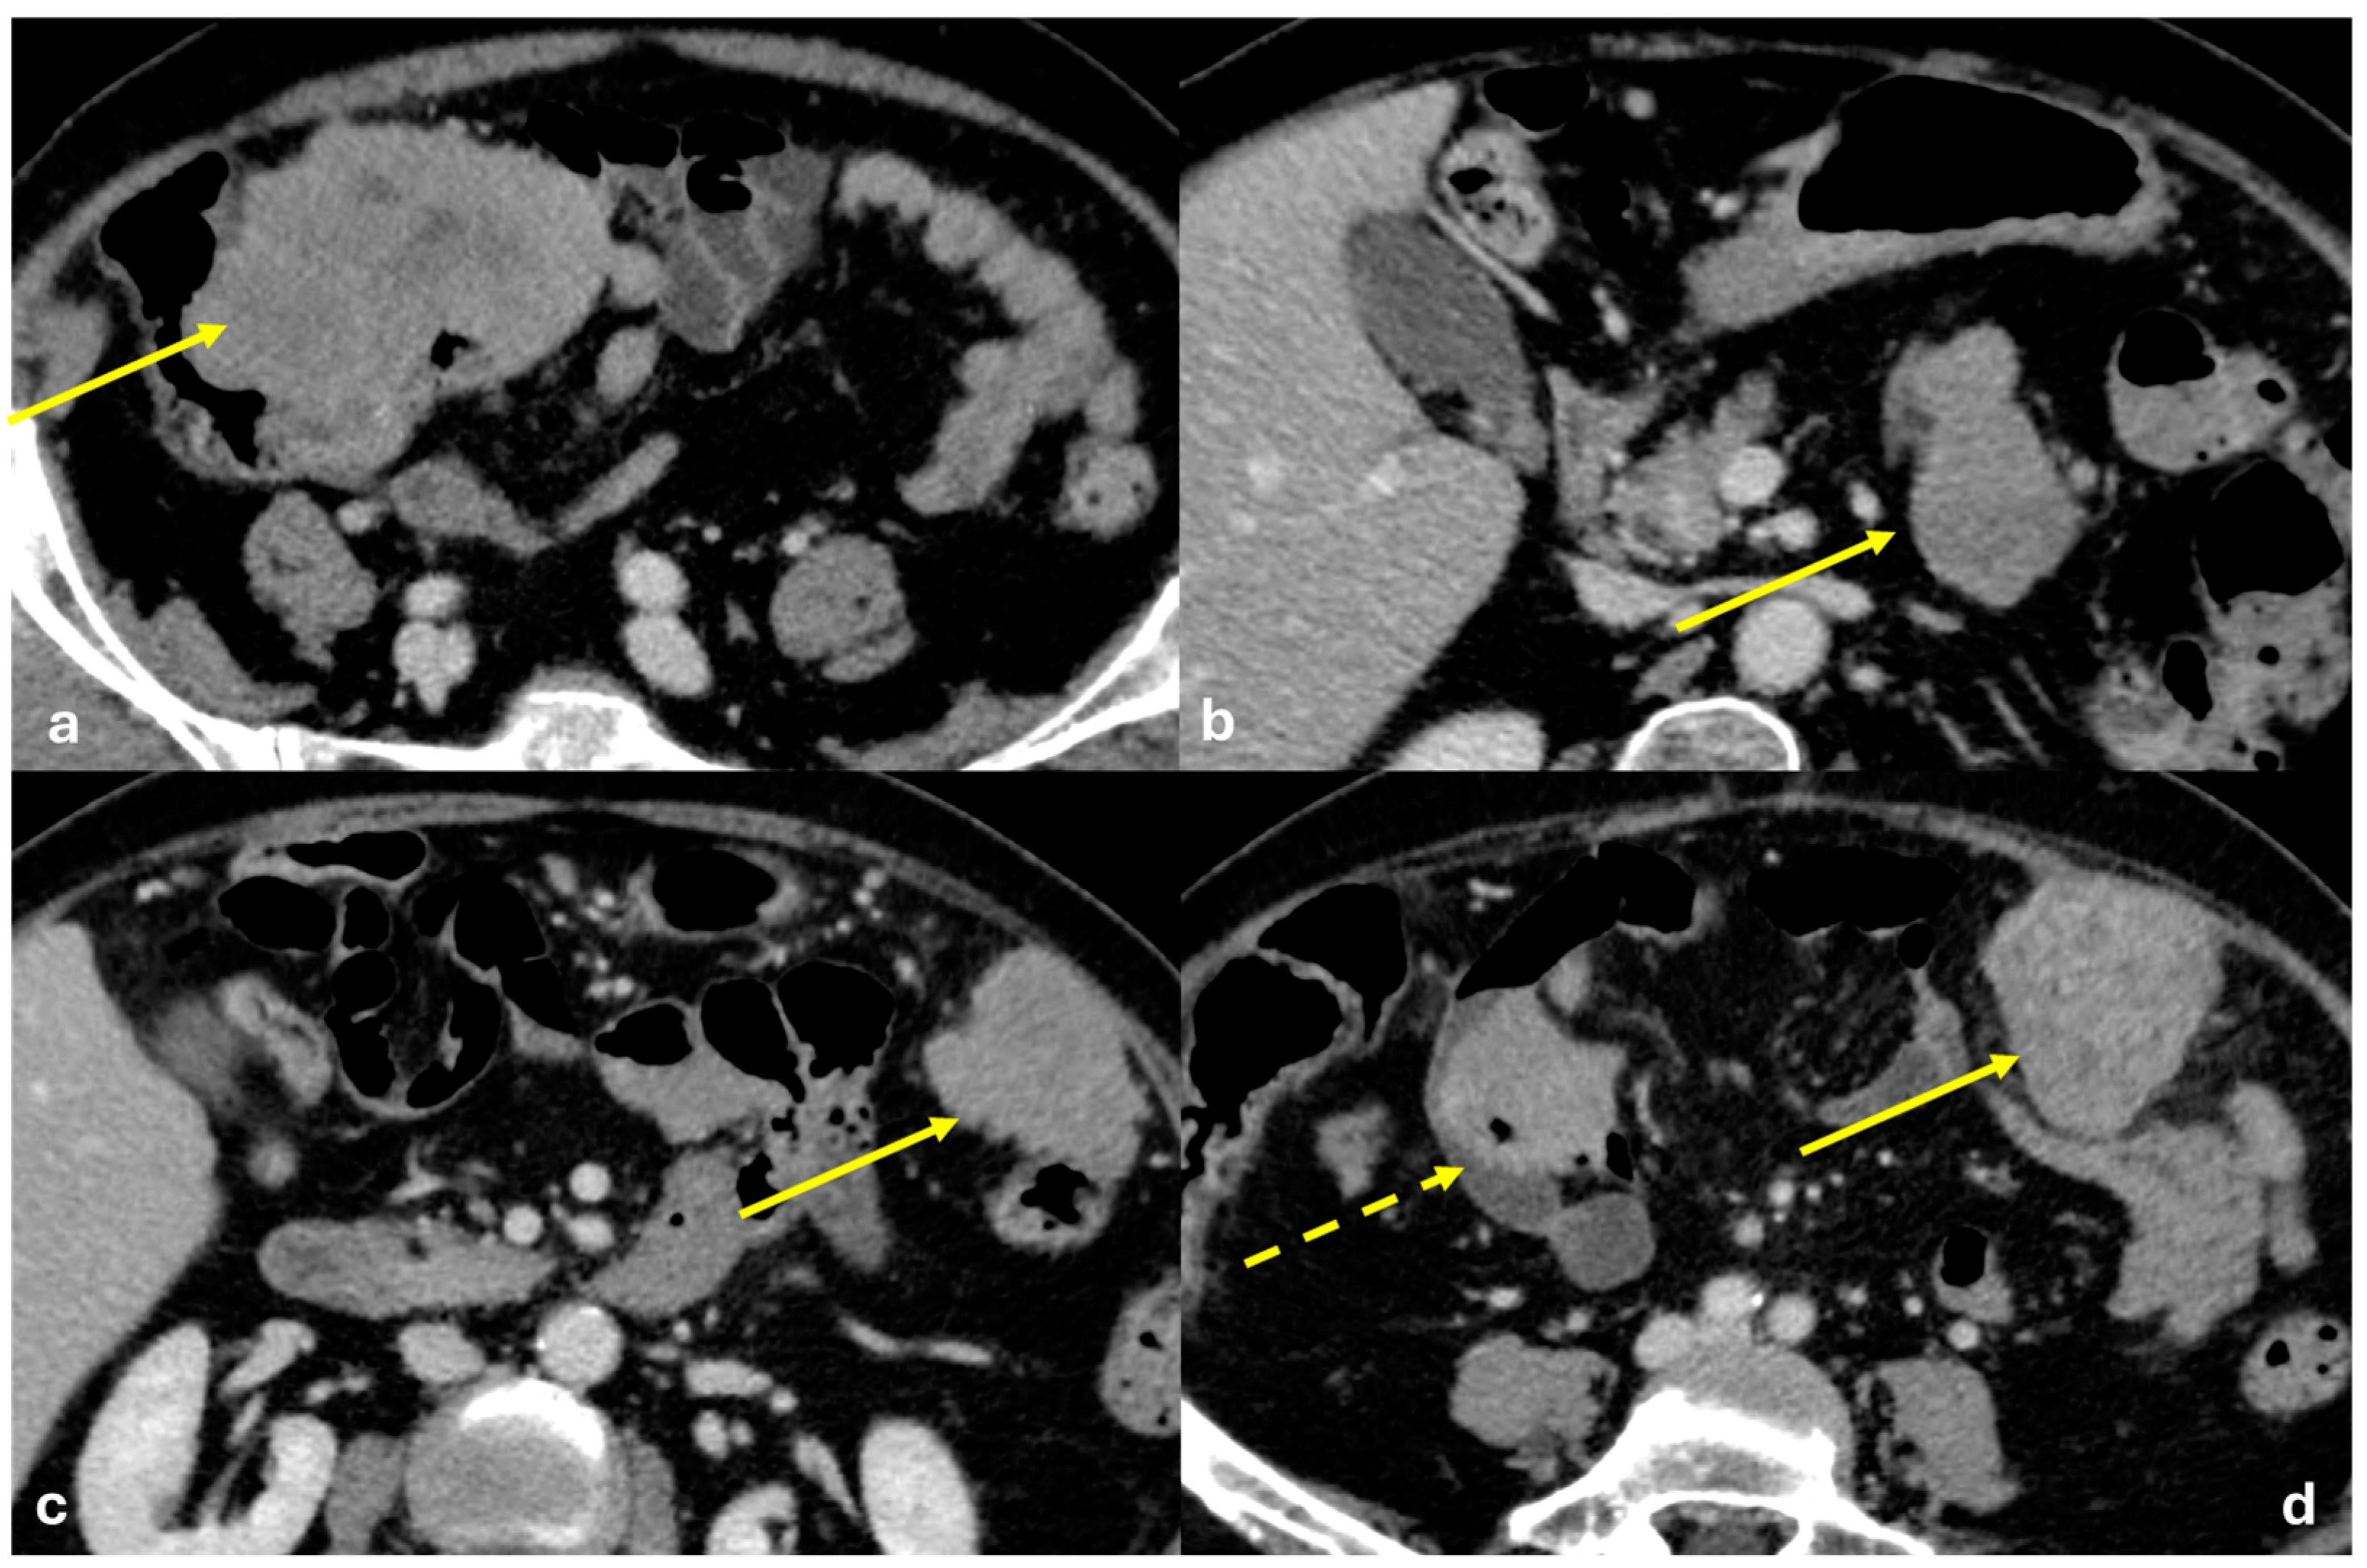

- Micro-nodular pattern: micro-nodules with a diameter ≤ 5 mm (Figure 1);

- Nodular pattern: nodules with a diameter > 5 mm (Figure 2a);

- “Omental cake”: nodular thickening of the omentum (Figure 2b);

- Plaque pattern: confluent nodular plaques, typically involving the lower surface of the right diaphragm (Figure 3);